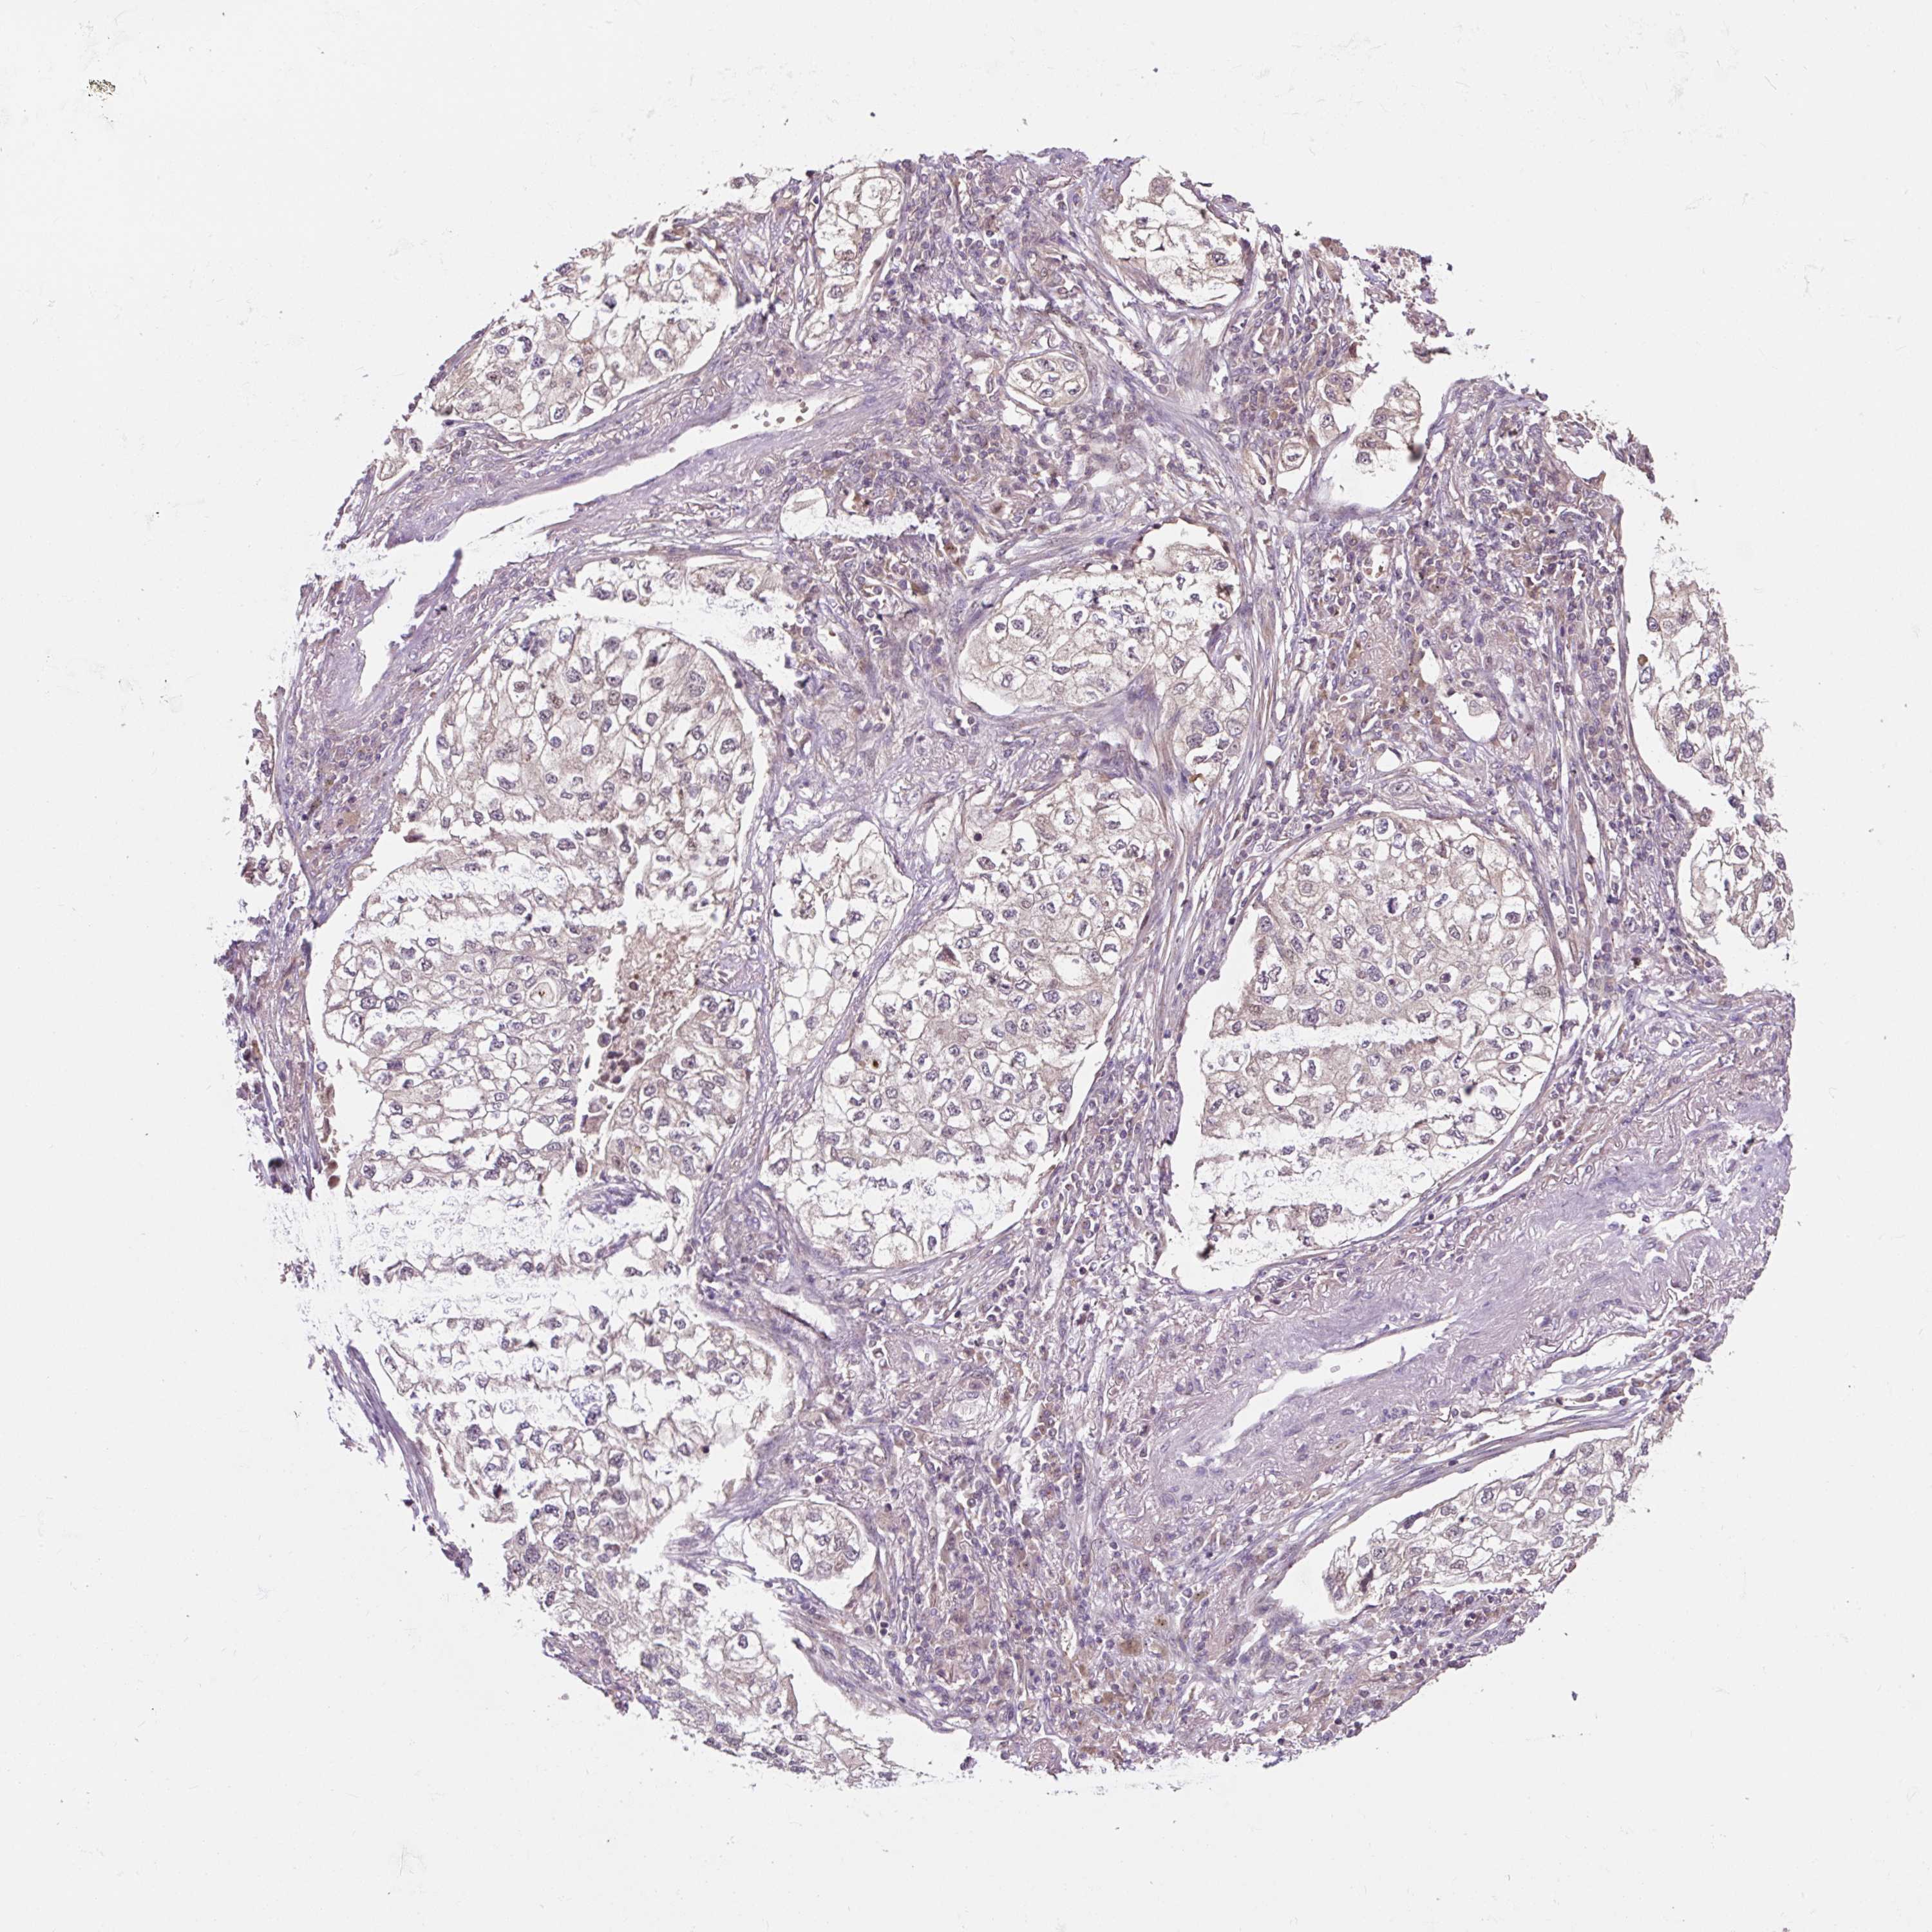

CANCER LUNG CANCER Show tissue menu

LUAD TCGA LUAD VALIDATION LUSC TCGA LUSC VALIDATION PROTEIN LUAD CPTAC PROTEIN LUSC CPTAC PROTEIN EXPRESSION

ANTIBODIES

AND

VALIDATION